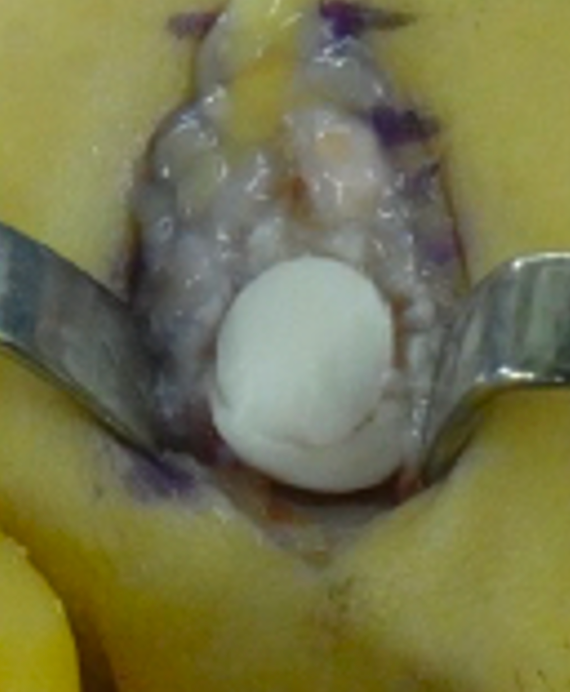

Autologous osteochondral transplantation

- A small plug of healthy cartilage and bone is taken from another joint (usually the knee)

- It is transferred to the damaged area of the metatarsal head

- Restores the joint surface without shortening the bone

- Associated with better movement, faster return to activity, and fewer complications in comparative studies

- Donor site problems are possible